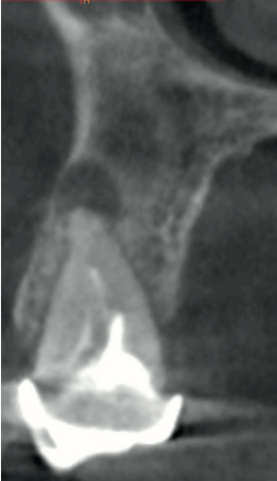

Caso clínico: se presenta el caso clínico de una mujer de 61 años, que acudió a consulta presentando dolor intenso en la zona del segundo premolar superior derecho (1.5). Se realizó la exodoncia del 1.5, usándose como diente donante para realizar una preservación del alveolo tras la extracción. Cuatro meses tras el procedimiento, se colocó un implante y se tomó una biopsia para realizar un análisis histomorfométrico. Un año tras la carga del implante se observaron buenos resultados clínicos y radiográficos.

Clinical case: a 61-year-old woman is presented, who came to private dental clinic presenting intense pain in the area of an upper bicuspid of the first quadrant (1.5). Exodontia of the 1.5 was performed, using it as a donor tooth to obtain the biomaterial to preserve its alveolus. After 4 months re-entry was performed and an implant was placed, harvesting a bone biopsy for histomorphometric analysis. One year post-loading, good clinical and radiographic results were shown.